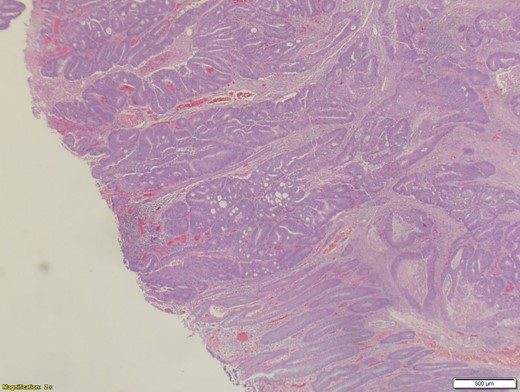

A 70-year-old female presented to the emergency department with complaints of diarrhea, vague, dull abdominal pain, unintentional weight loss and poor appetite. No hematochezia or melaena stated. Fecal occult is strongly positive in the ED. No endoscopies were found in her records. PMHx included COPD, osteoarthritis and DVT. Significant physical exam findings included mild, diffuse abdominal tenderness and RUQ palpable mass, and normal bowel sounds. Labs were significant for a hemoglobin of 5.7, hematocrit of 18.6% and CEA of 29.6. An abdominal/pelvis CT exhibited a 6 cm circumferential mass of the hepatic flexure (Figs 1–3). Two days later, a right hemicolectomy with en bloc pancreaticoduodenectomy was performed. Pathology showed adenocarcinoma stage IIIc (Figs 4–10). Post-operatively, an abdominal/pelvis CT showed bilateral pulmonary emboli and a 14 cm pelvic abscess. Bilateral lower extremity ultrasound showed low probability for DVT. Exploratory laparotomy was performed where the pelvic abscess was seen and extensive lysis of adhesions, resection of ileocolonic anastomosis for contained leak and ileostomy performed. Approximately 4 months after discharge, the patient passed away while in a long-term care facility.

When it comes to surgical intervention, there are three main methods of management of locally invasive colorectal cancers. These include hemicolectomy along with either en bloc pancreaticoduodenectomy, partial duodenectomy with either a pedicled ileal flap repair or direct suture. A 1947 study presented by Calmenson e Black, included a series of eight patients whom had locally advanced colon cancer with duodenal invasion. These patients agreed to a duodenal resection that resulted in a 0% survival rate after a year (three dying immediately in the post-operative period) [4]. The first case of right hemicolectomy with en bloc pancreaticoduodenectomy was described by Van Prohaska in 1953 [5]. Evidence shows that aggressive resection of adjacent organs along with a hemicolectomy has acceptable morbidity and mortality rates [6]. In comparison, a partial duodenal wall resection was associated with a poor outcome [7]. Even though complete resection remains controversial, microscopic examination of locally advanced colorectal cancers have shown to have a direct extension through the serosa of adjacent organs in 53.4%, whereas the remaining 46.6% showed a simple inflammatory adherence [8]. Since over 50% of locally advanced colorectal cancers resulted in a microscopic infiltration, a right hemicolectomy plus pancreaticoduodenectomy is strongly recommend for tumors that invade or are suspected to invade the duodenum and/or the pancreas [3]. However, when limited to the duodenum, a local duodenal resection is sufficient [9]. When an R0 resection was possible (achievable in 93% of all colorectal cancers), a poor outcome was avoided. However, patients with R1 or R2 resection have a 0% 5-year survival rate, compared to the 80.7% in R0 resection patients [8]. The greatest factor in the survivability of locally advanced colorectal cancer patients is when R0 resection is possible, as confirmed by Lehnert et al. [6]. Advanced age alone, apart from usually associated comorbidities, is not considered an absolute contraindication to multivisceral resection, considering the better overall results as opposed to more conservative approaches [1].